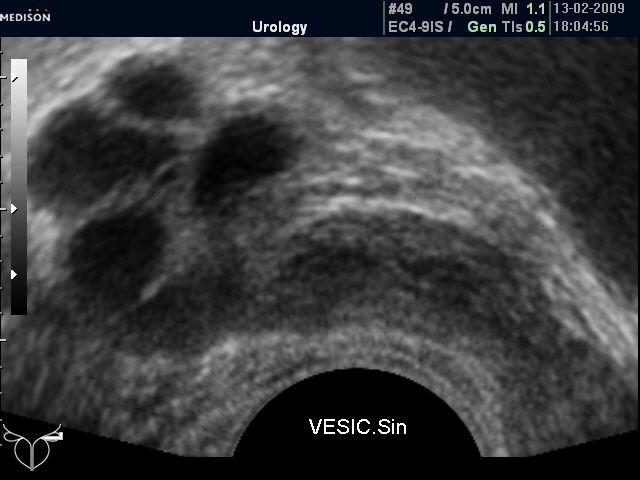

Досылаю фото семенных пузырьков.

Кистозная трансформация семенного пузырька